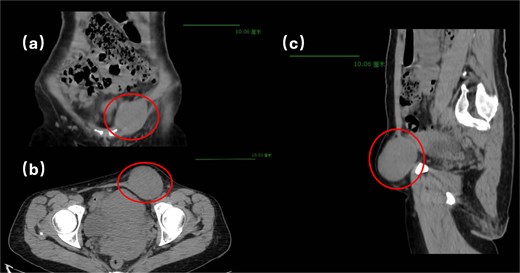

Physical examination revealed a soft, non-tender abdomen without hepatosplenomegaly or shifting dullness; normal bowel sounds were auscultated. A 5 × 5 cm firm, well-circumscribed mass with smooth surface contour and mild tenderness was palpated in the left inguinal region, demonstrating irreducibility and resistance to manual compression. Preoperative imaging modalities—contrast-enhanced computed tomography (Fig. 1) and grayscale ultrasonography (Fig. 2)—suggested a provisional diagnosis of uterine fibroid.

Surgical intervention comprised en bloc excision of the mass with the affected round ligament segment, followed by laparoscopic tension-free mesh hernioplasty (Fig. 3). Histopathological analysis confirmed uterine adenomyoma (Fig. 4). The patient was discharged on postoperative Day 5 following an uneventful recovery.

In this case, the patient exhibited no documented gastrointestinal symptoms—specifically, the absence of abdominal pain, bloating, nausea, vomiting, or alterations in bowel habits—throughout the disease course. Premenopausal menstrual cycles were characterized by regular 25- to 28-day intervals with physiological blood loss. Although adenomyotic lesions are typically estrogen-dependent and tend to regress after menopause, some patients may still experience subtle postmenopausal manifestations such as vague pelvic pressure or discomfort due to residual tissue changes [1]. Notably, this patient demonstrated complete resolution of gynecological symptoms postmenopause, with neither pelvic pain nor abnormal vaginal bleeding or discharge observed. Contrary to expected regression patterns, the left inguinal mass exhibited progressive enlargement, culminating in irreducibility necessitating surgical intervention. Although preoperative imaging likely suggested an incarcerated hernia of uterine fibroid origin, definitive histopathological diagnosis confirmed uterine adenomyoma.